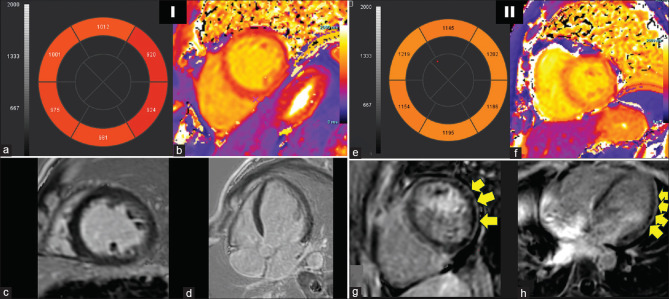

Results: With a mean age of 35.3 ± 12.2 years and a female preponderance (F:M = 2.4:1), the majority of the study population (77.4%) exhibited positive myositis-specific antibodies, whereas 45.2% had myositis-associated antibodies. Cardiac symptoms were reported by 45.2% of the cases, while 48.3% had an MDAAT cardiac Visual Analog Scale (VAS) score of ≥1, indicating potential cardiac involvement. Cases had significantly higher native T1 and T2 mapping values (1085.7 ± 57.7 vs. 1043.3 ± 36.1 ms, P = 0.002 and 52.9 ± 4.3 vs. 50.4 ± 2.6 ms, P = 0.011, respectively). Late gadolinium enhancement was seen in 6.4%. The native T1 value positively correlated with the MDAAT total score (ρ = 0.376, P < 0.014) and cardiac VAS score (ρ = 0.259, P = 0.038). A native T1 value ≥1048.25 ms has 72.7% sensitivity and 51.4% specificity (AUC = 0.711, P = 0.019) in detecting cardiac involvement.

Conclusions: Clinical parameters and CMR multiparametric mapping are shown to be correlated in this prospective investigation. It is the first study to look at the cardiac mapping parameters' sensitivity and specificity to MDAAT-based cardiac involvement. In the Indian population with IIM, it is the first assessment of cardiac involvement utilizing CMR. In IIM, this endeavor is expected to greatly improve early detection, prevention, and treatment of cardiac complications.